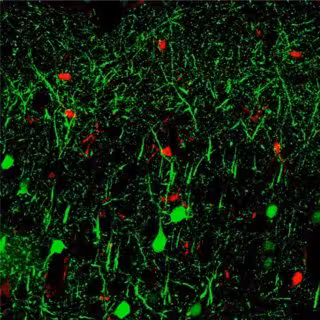

MicroARN 142

HUI-CHEN LU, INDIANA UNIVERSITY

En respuesta, el equipo realizó pruebas adicionales para estudiar un tipo específico de microARN (miroARN 142) que se elevó en el modelo de demencia. Así, descubrieron que la introducción de este microARN en el cerebro desencadena una neuroinflamación importante. "El resultado es importante, ya que muchos otros estudios han demostrado que la inflamación crónica contribuye a muchos tipos de enfermedades, incluida la neurodegeneración", ha añadido Lu.